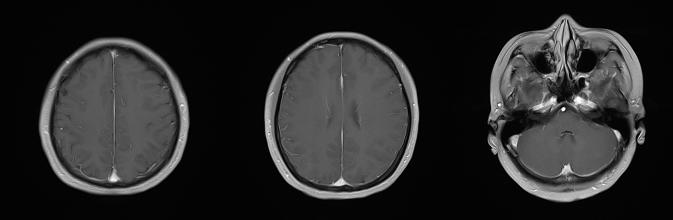

• 头颅MR(2025年3月27日):颅内病灶较前明显减少,余左侧小脑半球结节状异常信号,余显示不清,请结合临床。

乳腺cr是什么双优标杆!从PD到18 个月达颅内CR,瑞波西利改写32岁HR+/HER2-晚期乳腺癌患者命运_https://www.jmylbn.com_新闻资讯_第7张

图 2025年3月27日头颅MR

①治疗11个月后,2025年3月27日颅脑MR对比2024年4月14日颅脑MR,患者脑部转移灶减少,左侧小脑半球处病灶明显减小,达到部分缓解(PR),患者眩晕症状消失。